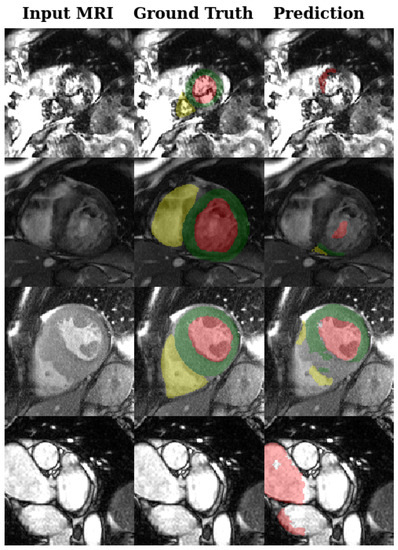

- Automated Cardiac Diagnosis Challenge (ACDC) data set [2]: This data set comprises 150 exams acquired at the University Hospital of Dijon (all from different patients). It is divided into 5 evenly distributed subgroups (4 pathological plus 1 healthy subject groups) and split into 100 exams for training, and 50 are held out set for testing. The exams were acquired using two MRI scanners with different magnetic strengths (1.5 T and 3 T). The pixel spacing varies from 0.7 mm to 1.9 mm with a slice spacing varying between 5 mm and 10 mm. An example of images with the different expert and non-expert annotations is shown in Figure 1.